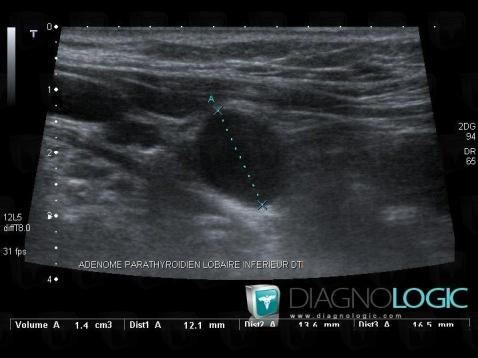

Parathroid adenoma, Thyroid / Parathyroid, US

Here is the specific information in the key image above:

- Diagnosis Parathroid adenoma, Location(s) Thyroid / Parathyroid, with gamuts